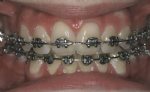

Behandlung mit weißen (zahnfarbenen) Brackets und goldenen Brackets

Die auf die Zähne geklebten Brackets sind in der Regel aus Stahl und daher silberfarbig. Stählerne Brackets sind besonders schlank und bieten eine sehr exakte Führung für die aktiven Elemente der Zahnspange. In manchen Fällen ist es auf Grund der beruflichen Situation des Patienten nötig, möglichst unauffällige, also zahnfarbene Brackets zu verwenden.

Auch die Verwendung goldfarbiger Brackets (und zum Teil auch Drähte) ist möglich und verbessert oft entscheidend die kosmetische Wirkung. Die Qualität derartiger goldfarbener Brackets ist dabei ähnlich gut wie die der silbernen.